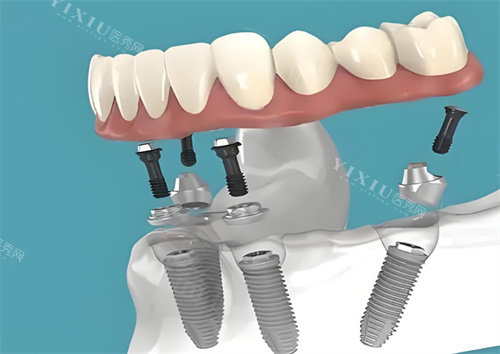

二、全口/半口种植价格:从3万到30万,方案差异大

1.半口种植

国产半口:4万元起(4-6颗植体支持)

韩国半口:5万元起(All-on-4技术)

瑞士半口:10万元起(个性化桥架设计)

实例对比:

65岁张先生选择韩国登腾All-on-4,总费用5.2万元,术后当天可进食软食。

58岁李女士选择瑞士ITI个性化方案,费用9.8万元,但牙龈退缩率比韩国方案低40%。

2. 全口种植

传统种植:8万元起(8-12颗植体)

All-on-6即刻修复:15万元起(6颗植体支持全口桥)

穿颧穿翼种植:25万元起(适合无牙颌且骨量极差者)